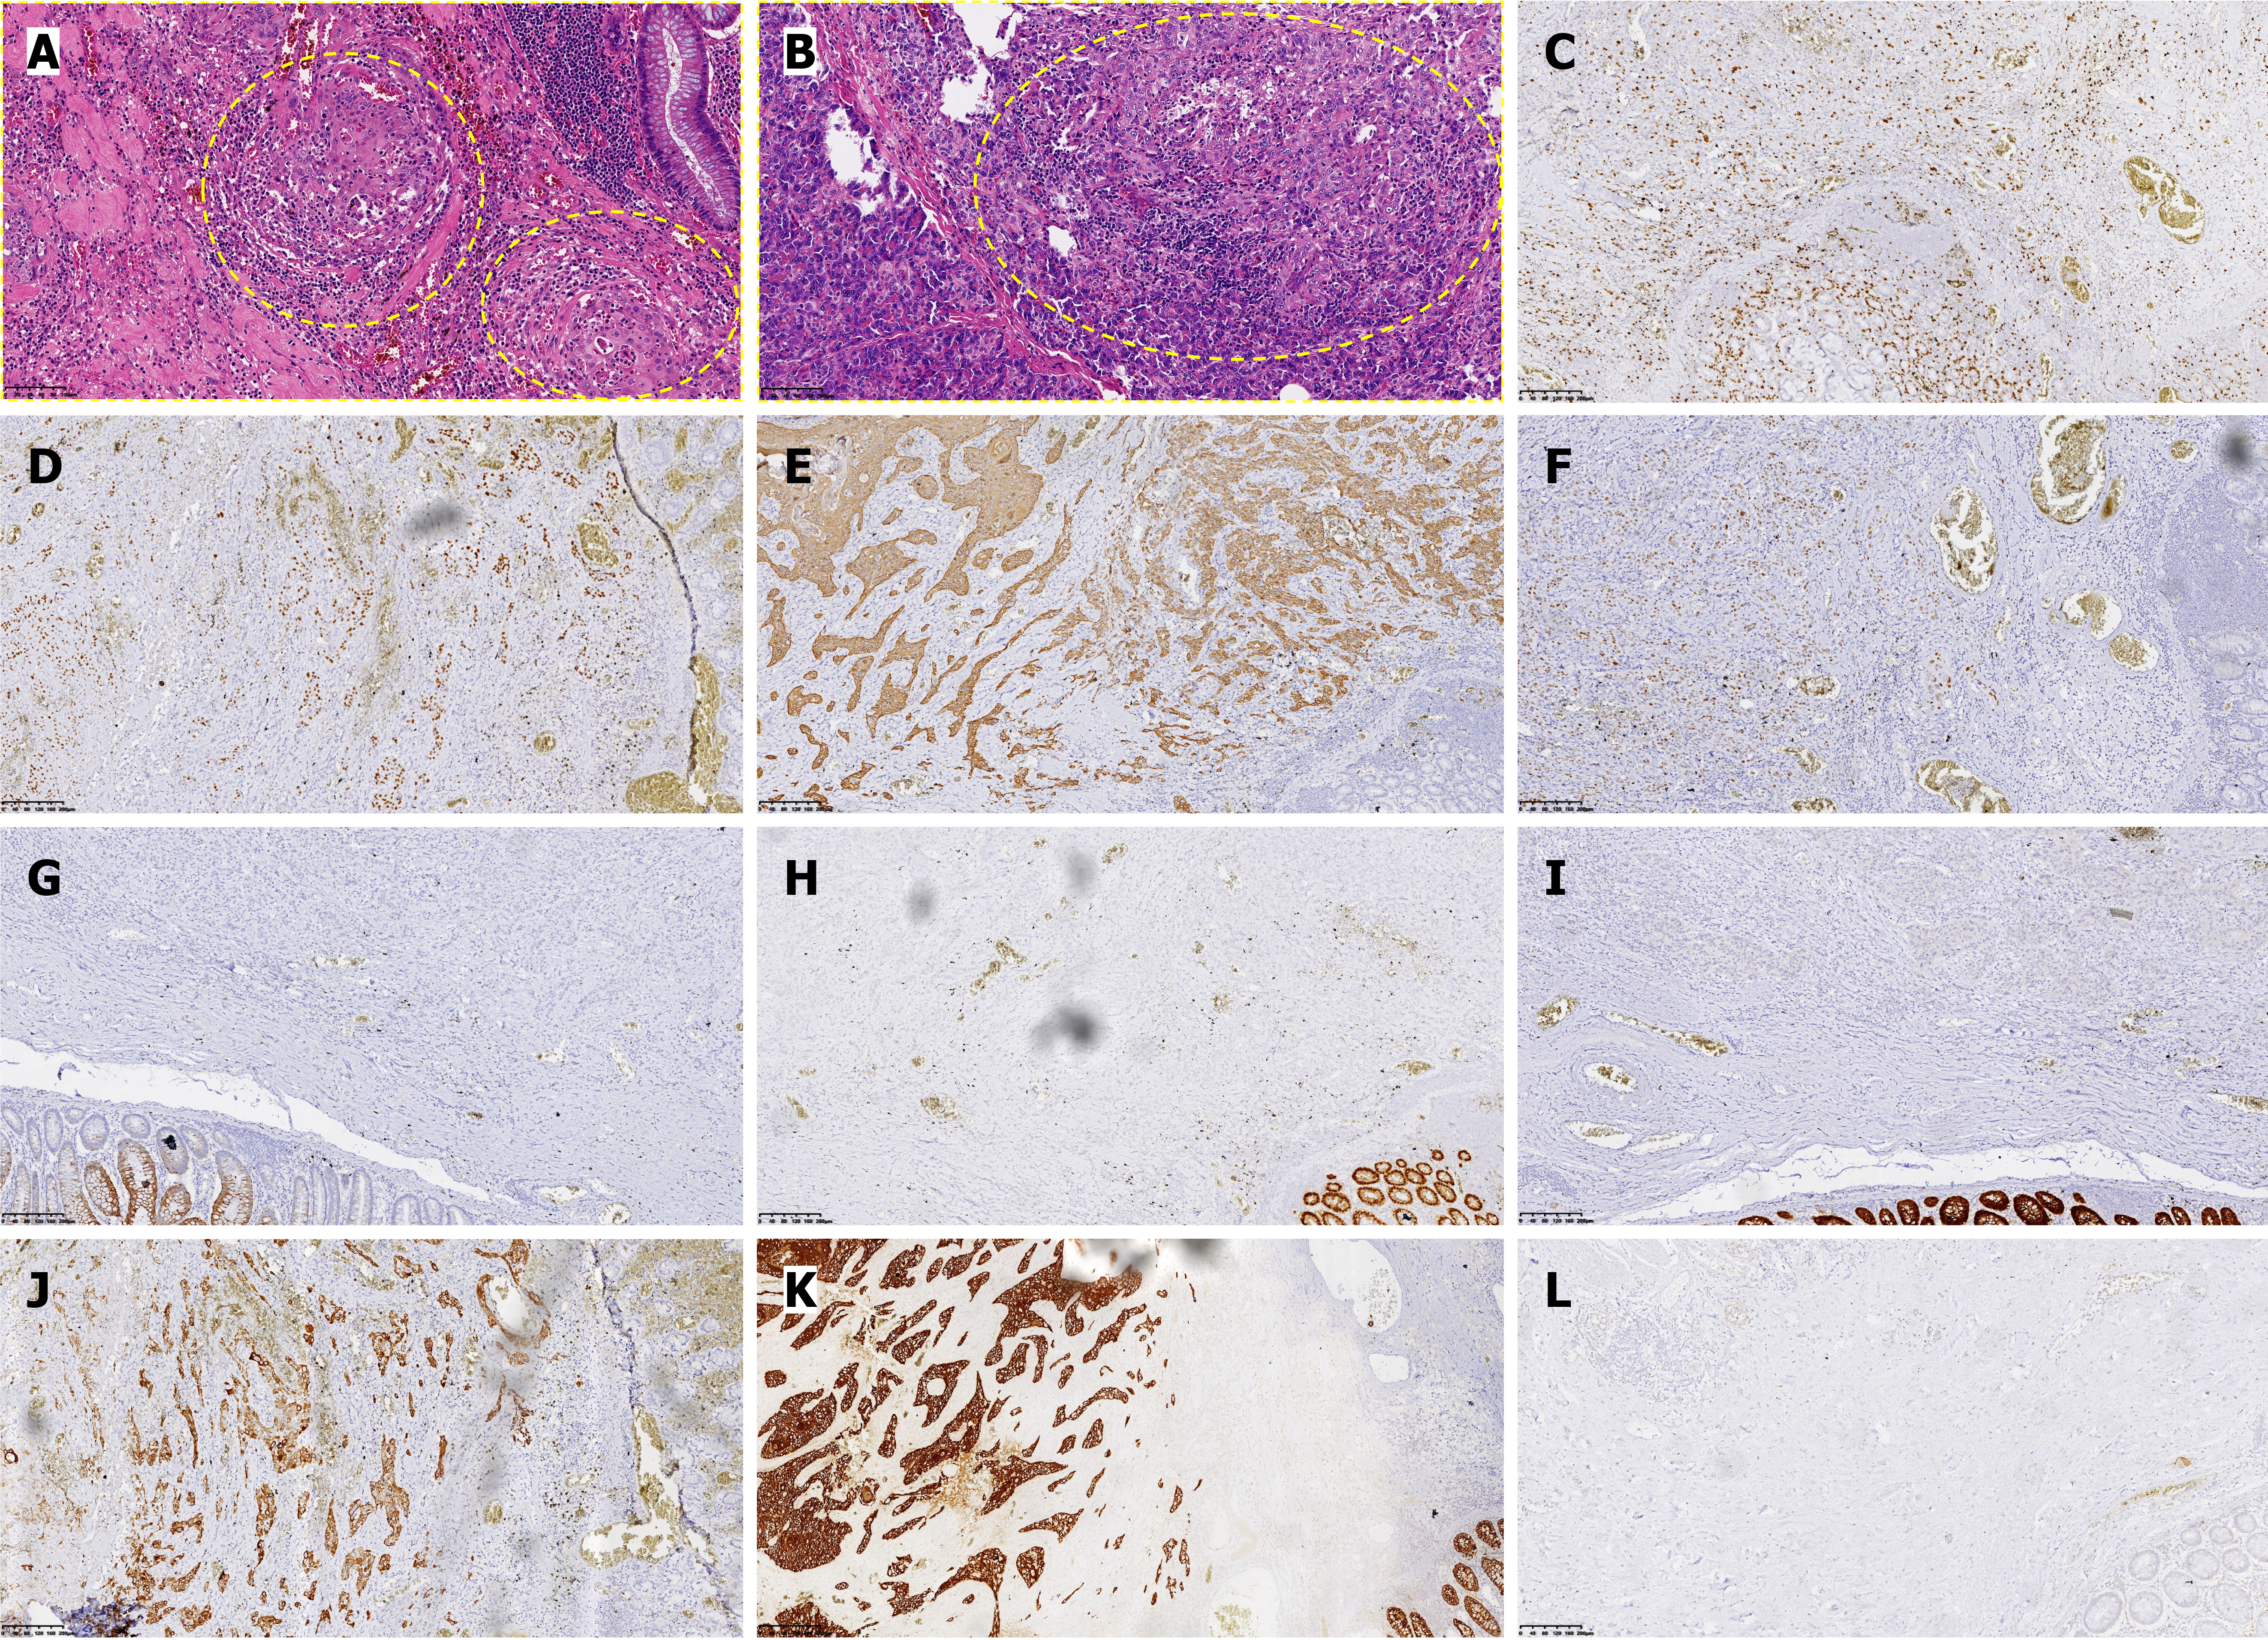

Postoperative pathology (Figure 2) confirmed tumor invasion through the entire intestinal wall and into the pancreas, with neural invasion (+). Immunohistochemical analysis demonstrated positive staining for squamous differentiation markers [P40, cytokeratin (CK) 5/6, P63] with strong pan-CK expression, along with CK7 positivity, while showing negativity for intestinal differentiation markers (CK20, caudal-type homeobox protein 2, villin) and somatostatin receptor 2. This immunoprofile supports the diagnosis of SCC and argues against a colorectal adenocarcinoma origin or neuroendocrine differentiation, with additional findings including a moderate proliferative index (Ki67 approximately 20%) and preserved vascular (CD34+) and lymphatic (D2-40+) architecture. Within 24 hours postoperatively, the patient developed agitation with elevated CRP and cardiac troponin I levels (Figure 3). Electrocardiography demonstrated acute non-ST-segment elevation myocardial infarction, attributed to perioperative ischemic hypoperfusion exacerbated by concurrent intra-abdominal infection. Empirical antimicrobial therapy with ceftriaxone was initiated alongside continuous negative-pressure peritoneal irrigation. Adjunctive therapies included antiplatelet therapy (aspirin), lipid-lowering therapy (atorvastatin calcium), and coronary vasodilation (tanshinone). Nutritional Risk Screening (2002) revealed a score of 6 points, prompting intravenous administration of glucose, amino acids, vitamins, and fat emulsion. On postoperative day 5, purulent drainage fluid cultured multidrug-resistant Escherichia coli, while Doppler ultrasonography of the lower extremities revealed bilateral calf dorsal muscular venous thrombosis. Antimicrobial therapy was escalated to ertapenem based on antimicrobial susceptibility testing, with concurrent initiation of low-molecular-weight heparin anticoagulation. Amylase-negative abdominal fluid analysis excluded pancreatic leakage. Following comprehensive therapeutic inter

Although large-scale studies by Larkins et al[9] confirmed significantly prolonged overall survival with surgery plus adjuvant chemotherapy (hazard ratio = 2.66), our patient’s 3-month survival - attributable to postoperative complications precluding adjuvant therapy - exposes limitations in current therapeutic frameworks. Conventional chemotherapy regimens (e.g., 5-fluorouracil-based XELOX) exhibit limited efficacy in certain colorectal SCC cases, while emerging evidence supports the potential superiority of taxane-carboplatin regimens or programmed cell death protein-1 inhibitor-chemotherapy combinations[14-17]. The therapeutic role of radiotherapy in colorectal SCC remains inadequately defined, with limited high-quality evidence supporting its routine use. While definitive chemoradiation has demonstrated efficacy in rectal SCC (5-year local control rate: 72%, Sturgeon et al[18]), extrapolation to colonic SCC lacks robust validation. Furthermore, the immunohistochemical profile of this case (CK7+) correlates with findings by Singhal et al[19], where CK7 positivity, as demonstrated in this case (Figure 2J), correlates with epithelial-mesenchymal transition markers, suggesting a mechanistic link to metastatic potential[19], signifying its utility as a prognostic biomarker. Future directions should focus on the following: (1) Developing SCC-specific staging systems integrating molecular features (e.g., programmed death-ligand 1 expression, tumor mutational burden, CK7 status) and radiological assessments of invasiveness[12,17,19]; (2) Exploring neoadjuvant chemoradiation for locally advanced disease, informed by definitive chemoradiation strategies for rectal SCC[17]; and (3) Optimizing perioperative management to mitigate severe complications. Despite the unfavo